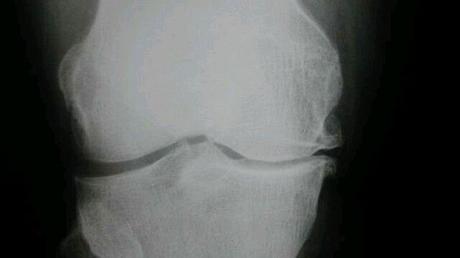

Esta es una pregunta que se ha planteado a lo largo de bastantes años. Con ser malo para las rodillas me refiero a padecer artrosis de rodilla, una enfermedad degenerativa de las articulaciones que aparece como consecuencia del desgaste de la articulación, que puede ser por un uso excesivo de la misma o bien por otra causa diferente; no obstante, a día de hoy todavía se desconoce el mecanismo exacto por el cual se produce esta enfermedad, por lo que todavía no podemos responder con total certeza a esa pregunta.

Los resultados fueron inesperados: los participantes que habían corrido de manera regular eran menos propensos a padecer artrosis de rodilla comparados con aquellos que no corrían regularmente; en concreto, el 29’8% de los no-corredores padecieron artrosis de rodilla, mientras que el porcentaje se redujo en los corredores a un 22’8%.

Por tanto, correr puede ser un factor protector contra la artrosis de esta articulación en lugar de ser un factor de riesgo como firmemente se creía. Ahora bien, el estudio no determina si el ejercicio regular puede empeorar una artrosis de rodilla ya existente en el deportista.